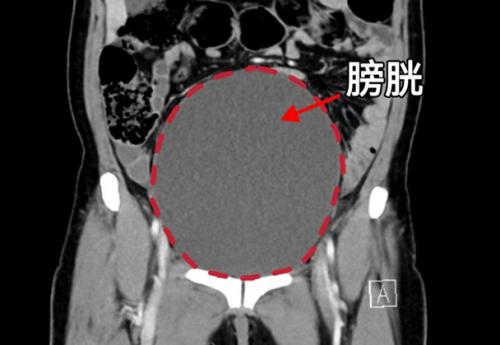

CT显示膀胱高度膨胀、尿道梗阻

“患者20余年前就因咳嗽后溢尿就医,诊断出子宫脱垂,因为担心手术风险一直没有接受治疗,半个月之前老人出现尿频、尿痛、排尿困难,忍着没和家里人说,直到6月4日,发现有肿块从阴道口脱出,内裤上有血迹才被家人送医。”据香港马会app 妇产科三区主任魏馨介绍,经检查发现患者为子宫脱垂三度(Ⅳ期),子宫和阴道前后壁完全脱出阴道口,由于脱出的组织压迫尿道,造成尿道梗阻、尿潴留、泌尿系感染,同时还合并有支气管扩张并感染、低蛋白血症、轻度贫血等情况。